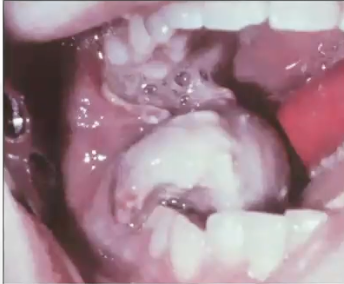

What is this image showing?

Huge expansion and swelling in left mandible area seen in chondrosarcoma